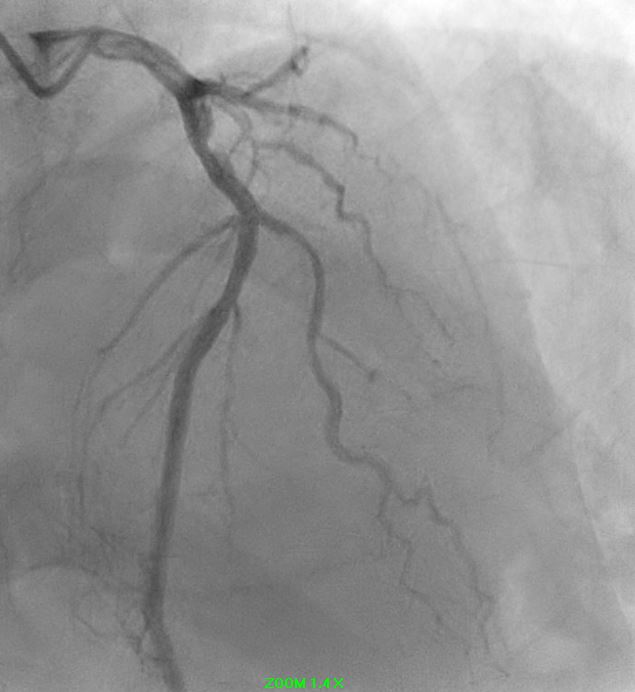

Angiographic assessment showed a normal left main stem, with severe proximal LAD disease exhibiting moderate calcification and providing retrograde collateral supply to both RCA and LCx. The LCx demonstrated severe mid-segment disease with subtotal occlusion of the obtuse marginal 1 (OM1) branch. The RCA showed severe proximal disease and total occlusion of the posterolateral(PL) branch.

Initial engagement with a JR3.5/6Fr guiding catheter provided suboptimal support; this was switched to a SAL 0.75/6Fr guide, which offered only modest improvement. Lesion predilatation was performed with non-compliant balloons (0.85/15 mm and 1.5/15 mm) assisted by a guide extension catheter. Intravascular ultrasound (IVUS)revealed a distal reference vessel diameter of 3.0 mm and proximal reference of 3.5 mm, with evidence of white thrombus at the mid RCA. Further lesion preparation was performed using Naviscore balloons (3.0/15 mm distally and 3.5/15 mm proximally),achieving satisfactory luminal gain. A repeat IVUS run confirmed resolution of the white thrombus. Based on this, a drug-coated balloon(DCB)-only strategy was chosen. EssentialPro DCBs (2.0/40 mm for distal-mid segment, and 3.5/40 mm for mid-proximal segment) were successfully delivered and deployed. Post-procedure IVUS demonstrated significant improvement in minimum lumen area (MLA)—from 2.91 mm©÷to 4.07 mm©÷ (distal) and 1.60mm©÷ to 6.93 mm©÷ (proximal).